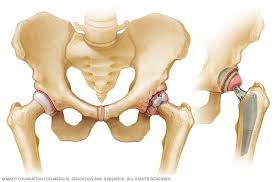

Hip replacement surgery can be performed as a total replacement or a hemi (half) replacement. In a hip resurfacing surgery, the implant is smaller, and less normal bone is removed. Learn what to expect when preparing & undergoing surgery. Albright discusses alternatives to hip replacement surgery. This involves removing the damaged surfaces of the bones inside the hip joint and replacing them with a metal surface.

Hip revision (a repeat hip replacement) surgery involves replacing your artificial hip joint if it's become loose, infected or worn out. Hip replacement surgery can be performed as a total replacement or a hemi (half) replacement. Alternatives to hip replacement surgery include conservative management, hip resurfacing, hemiarthroplasty, and viscosupplementation. Hip replacement surgery involves replacing the hip joint with new artificial joint parts. Hip replacement surgery and hip resurfacing are often the only surgical options presented to a patient to deal with their debilitating pain, though hip the innovative regenexx procedures restore hip function and mobility and decrease pain without the need for surgery by regenerating damaged. Direct anterior total hip replacement surgical procedure video. The most common conservative alternatives to hip replacement surgery are assistive devices (canes or walkers) to reduce stress on the affected hip there are both surgical and nonsurgical options to treat a herniated disc. Statistics and hip replacement therapy. Surgery and increase hip function. Some joint preservation procedures are newer and considered experimental, dr. A hip replacement procedure is a major surgical operation that is usually only reserved for cases where alternative therapies have failed. Hip replacement surgery is one of the most successful modern orthopedic surgical procedures. Lifestyle and medical options can help reduce discomfort and slow the damage.

Learn about hip replacement surgery, total hip replacement and partial hip replacement. Before opting for knee replacement surgery, it's important to consider all your options. Last updated may 24, 2019by howard j. Nonsurgical treatments include medication and going to a chiropractor. There is an alternative type of surgery to hip replacement, known as hip resurfacing. Hip replacement surgery can be performed as a total replacement or a hemi (half) replacement. Have you considered all the hip replacement alternatives available? Knee assessment and hip mechanics online course: Hip replacement surgery involves replacing the hip joint with new artificial joint parts. Some examples of the alternative approaches to treating damaged or painful hips are described below. Hip replacement is a surgical procedure in which the hip joint is replaced by a prosthetic implant, that is, a hip prosthesis. How long you stay in the hospital or surgical center after your surgery depends on many factors, including your overall health. Hip replacement surgery removes damaged of a hip joint & replaces them with new parts.

Lifestyle and medical options can help reduce discomfort and slow the damage. Hip replacement surgeries use modern biomaterials. Hip replacement surgery removes damaged of a hip joint & replaces them with new parts. Hip replacement surgery is one of the most successful modern orthopedic surgical procedures. Nonsurgical treatments include medication and going to a chiropractor. Hip resurfacing surgery is an alternative to standard hip replacements for patients with severe arthritis. The difference lies in the way it is because the surgical exposure, preparation of bone, and placement of the component with cement may cause this bone to be more vulnerable. Conservative management, which is aimed at delaying the need for surgery and, in a few cases may be sufficient for you to manage for many years. Alternatives to hip replacement surgery include conservative management, hip resurfacing, hemiarthroplasty, and viscosupplementation. In a hip resurfacing surgery, the implant is smaller, and less normal bone is removed. Some examples of the alternative approaches to treating damaged or painful hips are described below. Before opting for knee replacement surgery, it's important to consider all your options. Hip replacement may be an option if your hip pain interferes with daily activities and nonsurgical treatments haven't helped.